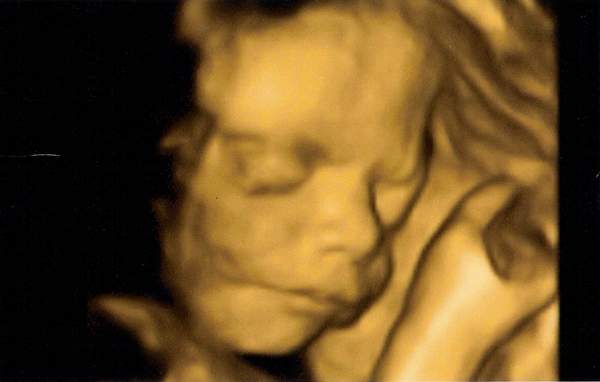

moja ROKSANKA